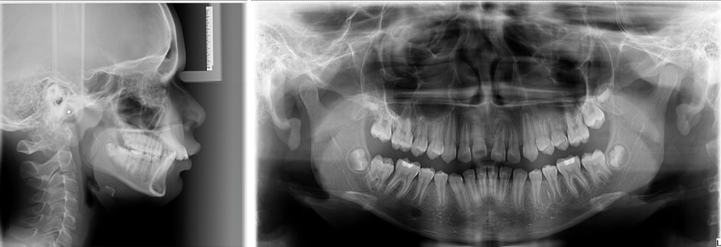

DOCUMENTAÇÃO ORTODÔNTICA

É um conjunto abrangente de registros diagnósticos utilizados para avaliar a condição dentofacial de um paciente, planejar o tratamento ortodôntico e monitorar o progresso ao longo do tempo realizado pelo Ortodontista. Criamos alguns tipos de documentação para facilitar a sua solicitação. Veja qual encaixa melhor para o seu paciente.

(PAN + TELE + 1 ANÁLISE + 6 FOTOS + PASTA SIMPLES)

(PAN + TELE + 2 ANÁLISE + 2 PERIAPICAIS ANTERIORES + 6 FOTOS + MODELO DE ESTUDO + PASTA SIMPLES + CAIXA SIMPLES)

(PAN + TELE + 2 ANÁLISE + 2 PERIAPICAIS ANTERIORES + 4 INTERPROXIMAIS + 6 FOTOS + MODELO DE ESTUDO + PASTA PVC + CAIXA PVC)